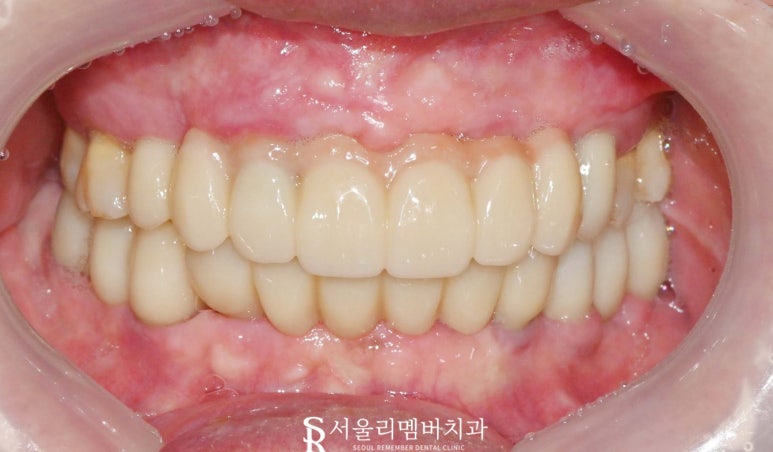

골 유착이 충분히 되었다면

상부에 지르코니아 크라운을 수복하겠습니다.

치아의 장축이 길어져 보이고 웃을 때도

어색하거나 부자연스러울 수 있다는 생각에

신림역 치과 자체 기공실에서는

윗부분에 선홍빛의 치은라인을 형성해 주었습니다.

윗입술이 일정 부분을 가리기 때문에

보다 자연스러움을 얻을 수 있습니다.

환자께서는 고기를 제일 먹고 싶어 하셨는데요.

이제 고기 마음껏 드셔도 좋습니다 :)